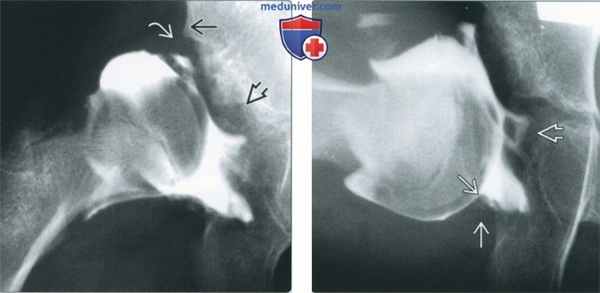

(Слева) Артрография, передне-задняя проекция, маленький ребенок: визуализируются уплощение крыши вертлужной впадины и гипертрофия суставной губы. Дефекты накопления в центре соответствуют гипертрофированной круглой связке и жировой подушке.

(Справа) Артрография, боковая проекция с отведением бедра, маленький ребенок: определяется нарушение отведения вследствие гипертрофии жировой подушки и круглой связки, а также деформации суставной капсулы по типу «песочных часов».